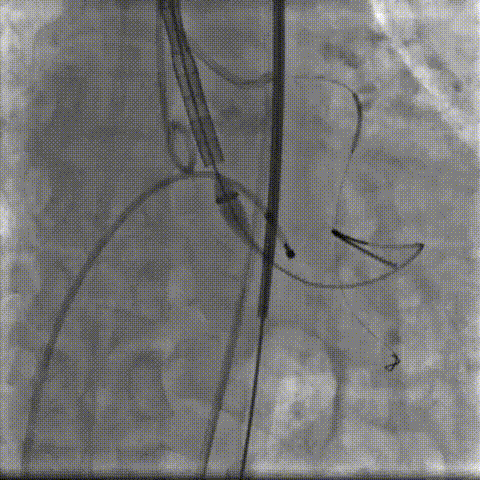

术中影像:

双侧侧髂血管造影血管纤细

LCA保护下18mm球囊预扩,扩张充分,瓣叶向LCA开口偏移;输送器过弓顺利。

瓣环下精准定位稳定释放,瓣膜工作位造影考虑瓣叶推挤LCA阻挡临界状态,释放“烟囱支架”。

瓣膜稳定脱钩,20mm球囊后扩,“烟囱支架”Kissing,后扩后支架形态改善。

左髂动脉“翻山“,造影+覆膜支架预备伴随保护下顺利退鞘,造影观察无血管损伤,手术顺利结束。